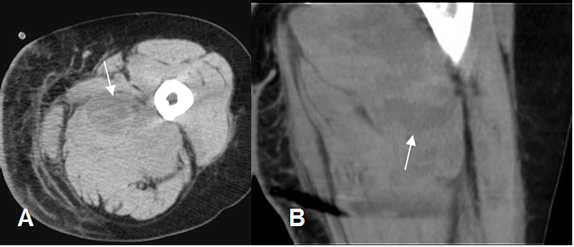

Fig 11. Hematoma muscular.

A: TAC axial y B: TAC reconstrucción coronal. Engrosamiento del músculo vasto interno, con formación de colección, que corresponde a hematoma.